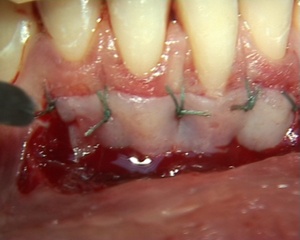

L'indication de greffe épithèlio-conjonctive a été posée pour traiter une récession gingivale. L'auteur utilise pour le prélèvement du greffon l'épitome de Klewansky et pour la protection du site donneur de l'histoacryl. La protection du site receveur est assurée par un pansement temporaire photopolymérisable